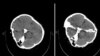

این گزارش در حالی منتشر می شود که خبرگزاری فارس -نزدیک به سپاه پاسداران- در روز ۲۸ شهریور، اصالت تصاویر سیتیاسکن مغزی مهسا امینی را که یک گروه هکری یافته و منتشر شده بود، تأیید کرده اما مدعی شده بود که «هیچ شواهدی از ضربه به سر و خونریزی در این تصاویر به چشم نمیخورد».

در آن زمان شماری از متخصصان از جمله رئیس شورای هماهنگی نظام پزشکی استان هرمزگان پس از بررسی این تصاویر، جانباختن مهسا امینی را از عوارض ناشی از ضربه مستقیم به جمجمه عنوان کرده بودند.